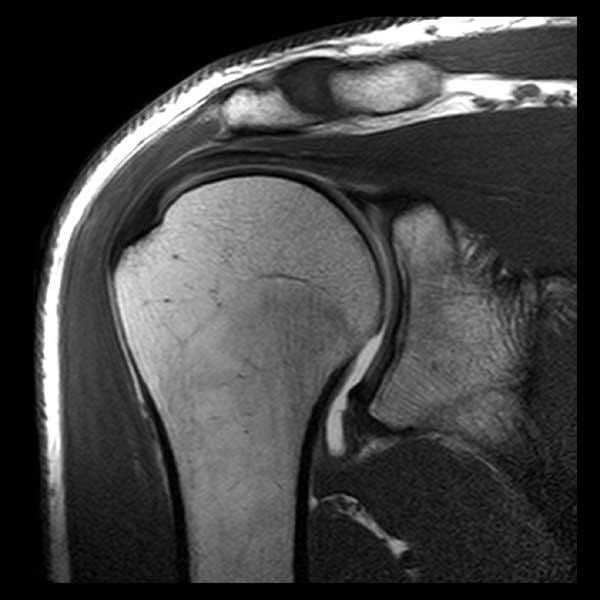

МРТ плечевого сустава — как делают и расшифровка результатов

МРТ плечевого сустава показана пациентам, жалующимся на боли и хруст в сочленении, скованность движений. При проведении процедуры используется оборудование, позволяющее получить высококачественные изображения костей, хрящей, связочно-сухожильного аппарата. МРТ, выполненная с контрастом, помогает оценить кровообращение в плече, визуализировать самые мелкие воспалительные очаги.

Для диагностики патологий опорно-двигательного аппарата обычно применяется рентгенография. Но она не всегда информативна при обследовании плечевого сустава, который имеет сложное строение. При проведении МРТ обнаруживаются не только деструктивные изменения костных и хрящевых тканей, но и повреждения синовиальной капсулы, связок, мышц, нервов.

Интерпретацией полученных результатов занимается врач лучевой диагностики. Расшифровка обычно не занимает больше 2 часов, однако при загруженности рентгенолога пациентам приходится ждать результатов в течение суток. Что показывает МРТ плечевого сустава:

- воспалительные очаги, деструктивно-дегенеративные изменения костей и гиалиновых хрящей визуализируются в виде интенсивно окрашенных областей;

- на воспаление указывают сформировавшиеся вокруг тканей полости;

- доброкачественные и злокачественные новообразования выглядят, как участки с более плотной структурой. Они интенсивно окрашены и локализованы на границе между костями и мышцами;

- при разрыве связок заметно смещение оторванных частей в суставную полость;

- разросшиеся края костных пластинок и обызвествленные области сигнализируют о необратимом разрушении хрящевых тканей, развитии остеоартроза;

- полное или частичное сращивание суставной щели указывает на анкилоз (неподвижность сочленения) и необходимость хирургического вмешательства;

- образование секвестров (омертвевших тканей) является характерным признаком инфекционного артрита;

- скопление жидкости в синовиальной сумке указывает на бурсит, а наличие выпота в полости сустава — на синовит;

- изменения теплообмена, также определяемые при обследовании, сопутствуют многим заболеваниям плечевого сустава.

Во время расшифровки результатов оценивается состояние костных поверхностей, выстланных хрящевыми тканями. В норме на них не должно быть выраженных дефектов. Исследуются и расположенные рядом с сочленением связки, сухожилия, нервные пучки, мышечные волокна. Изменения мягкотканных структур часто указывают на вялотекущий воспалительный процесс.